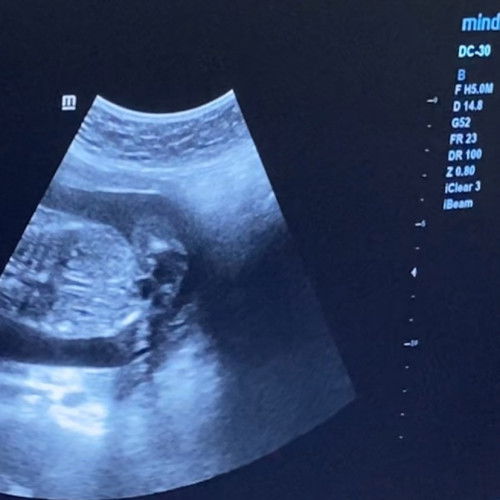

Contractions or not? 18 weeks preggy

Hello po. I'm 18 weeks preggy. Worried po ako kasi very tight po ang feeling ng tyan ko. Si baby po parang sumisiksik sa diaphragm area ko kaya nahihirapan po ako huminga. Is this normal po? Tapos paminsan minsan po may pain din po sa may bandang puson area. For 2 days ko na po sya nararamdaman. Although hindi tuloy2 pero yung discomfort, anjan po talaga. Baka po may maka help? Thank you po #Needadvice #askmommies